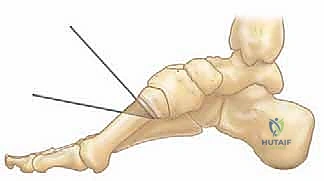

* نقل وتر جونز (Jones Transfer): نقل وتر العضلة الباسطة الطويلة لإبهام القدم إلى عنق المشط الأول لرفع مقدمة القدم وتخفيف الضغط.

* نقل العضلة الشظوية الطويلة إلى القصيرة (Peroneus Longus to Brevis Transfer): لتقليل القوة التي تسحب المشط الأول للأسفل.